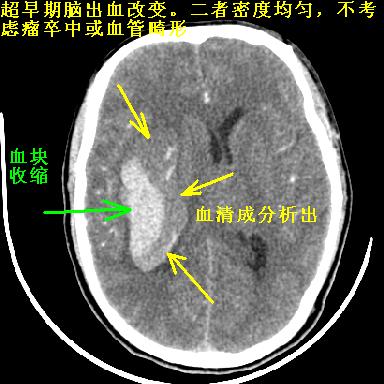

另附部分资料:“血液溢出血管外形成血肿,其内含有大量血红蛋白、血浆白蛋白,球蛋白,因这些蛋白对x线的吸收系数高于脑质,故ct呈现高密度阴影,ct值达40~90h,最初高密度灶呈非均匀一致性,中心密度更高,新鲜出血灶边缘不清。基底节区血肿多为“肾”型,内侧凹陷,外侧膨隆,因外侧裂阻力较小,故向外凸,其它部位血肿多呈尖圆形或不规则形”